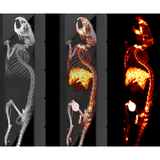

The X-CUBE is our high throughput CT “work horse”. It allows for fast whole body mouse and rat CT imaging at extremely low dose and excellent soft tissue contrast.

Light weighted thanks to a self-shielded imaging unit it is a truly mobile in vivo scanner. Advanced workflows such as gated and dynamic contrast enhanced imaging can be achieved in a functional and integrated set up. Our iterative reconstruction techniques are available in standard as well as expert user mode. Intuitive and wireless acquisition software combined with our multimodal small animal bed allow for easy and modular multimodal imaging along with the γ-CUBE (SPECT) and β-CUBE (PET).